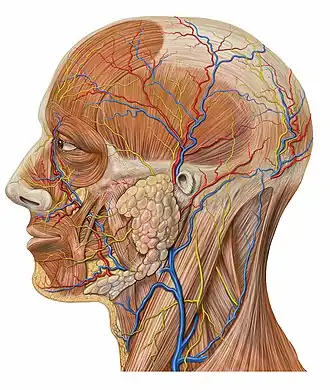

The arteries of the face and scalp (angular artery labeled at center right) | |

Lateral head anatomy detail

Lateral head anatomy detail -